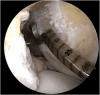

Graft-tunnel mismatch (GTM) is a known technical challenge that can occur with anterior cruciate ligament reconstruction when using a patellar tendon autograft. Two-incision anterior cruciate ligament reconstruction is a well-established technique with excellent outcomes and can serve as an excellent tool to prevent GTM. Traditionally, 2-incision femoral tunnel drilling has been performed using an over-the-top guide through a lateral incision, but more modern retrograde reamer guides can allow this to be done percutaneously. We detail how a minimally invasive 2-incision femoral tunnel drilling technique can be used in patients with patellar tendon lengths that are longer than average to avoid GTM.